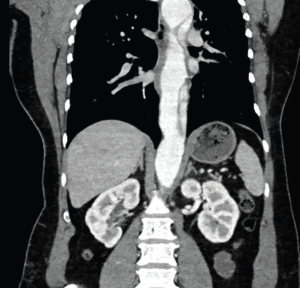

A 40-year-old woman with a history of untreated hypertension presented by ambulance after she was thrown from an ATV at unknown speeds and then crushed by the vehicle. The vehicle had no seatbelt or airbags, she was not helmeted, and she did not hit her head or lose consciousness. She reported 10/10 pain localized to her right arm and right flank, with no other complaints. On arrival, she was stable, airway breathing and circulation were intact, and Glasgow Coma Scale was 15. Initial vitals: HR 90, BP 161/142, RR 24, SpO2 100 percent on room air, afebrile. Primary survey was remarkable for an obvious deformity to the right forearm. Her secondary survey was remarkable for scattered abrasions and moderate bilateral flank tenderness. Her focused assessment with sonography for trauma was negative with bilateral lung sliding. The patient was neurovascularly intact throughout, with right upper extremity motion limited due to pain. Initial anteroposterior (AP) chest radiograph demonstrated no mediastinal widening, tracheal deviation, or pneumothorax. Plain film scout images of right upper extremity demonstrated a midshaft radius fracture.The CT scan of the chest, abdomen, and pelvis revealed a large traumatic Stanford type B aortic dissection. The patient was immediately started on esmolol and nicardipine drips with a systolic pressure goal of 120 mmHg. She was emergently transferred to a Level 1 trauma center by air ambulance, accepted by trauma surgery, and followed closely by vascular surgery.

ACEP Now: Vol 43 – No 07 – July 2024This case highlights the importance of recognizing concomitant trauma beyond a distracting injury. Traumatic aortic injury (TAI) is the second most common cause of mortality in non-penetrating traumatic injury; nearly 80 percent of cases die before hospitalization, and, of those who are hospitalized, mortality remains greater than 45 percent, with untreated mortality increasing one percent per hour.3,4 Most individuals suffering TAI are young males injured in motor vehicle accidents or falls.2 Although the most common originating site of a traumatic aortic dissection is distal to the left subclavian artery (LSA), in this case the proximal tear originated immediately upstream from the subclavian and distal to the left carotid artery.2 Plain radiographs of the chest may demonstrate findings of TAI—mediastinal widening, tracheal displacement, abnormal imprints of the aortic arch—but have low sensitivity and specificity, as reflected by normal findings in this case.2 The gold standard for imaging traumatic aortic injury is contrast-enhanced CT, with trans-esophageal echocardiogram being the second-best option if CT is not immediately available.2 Despite the ready availability of trans-thoracic echocardiogram (TTE) and its ability to capture aortic root dilation, cardiac tamponade, and dilation of the descending aorta and abdominal aorta, the sensitivity and specificity of TTE in traumatic aortic injury remains low and should not be relied on.2,3 In this case, aortic dissection was visualized neither on initial bedside nor on repeat inpatient TTE, despite operator knowledge of a known lesion and extensive operator training.